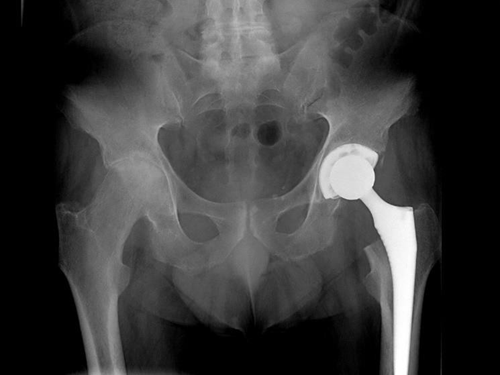

An X-ray of the hip revealed advanced bilateral osteoarthrosis, classifying both hip joints as grade 3 according to Tonnis' classification (Figure 2).

Figure 2 Pre-arthroplasty hip X-ray.